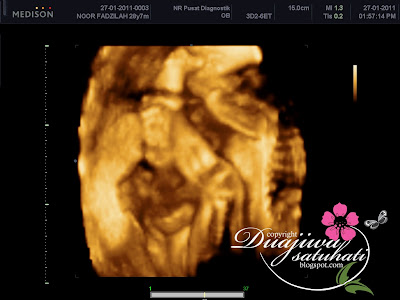

neh beberapa pic baby yg dpt ms bt 3d/4d scan di Shah Alam....jum tgk pic..

Masa nak tgk muka dia...punya la payah..dia tutup betul2..mula2 sebelah tangan ajer lepas tuh tgk..nk letak 2 tgn..marah ke..malu ke ekkk....tgk dia..ehehhee...

Makan masa jugak la nk mitk tgk muka dia..nak cek kan..tgk hidung mata mulut cner...tuh dh turun tgn sebelah....

Nha...baru bg tgk eh...malu ke baby ekk..ekekekkee.....

kalo tgk gini...gaya2..rupa bentuk ada sket cm addin....mulut..dh kompom!!! mcm mulut papa..kecik2..comey2..hahhhaa...